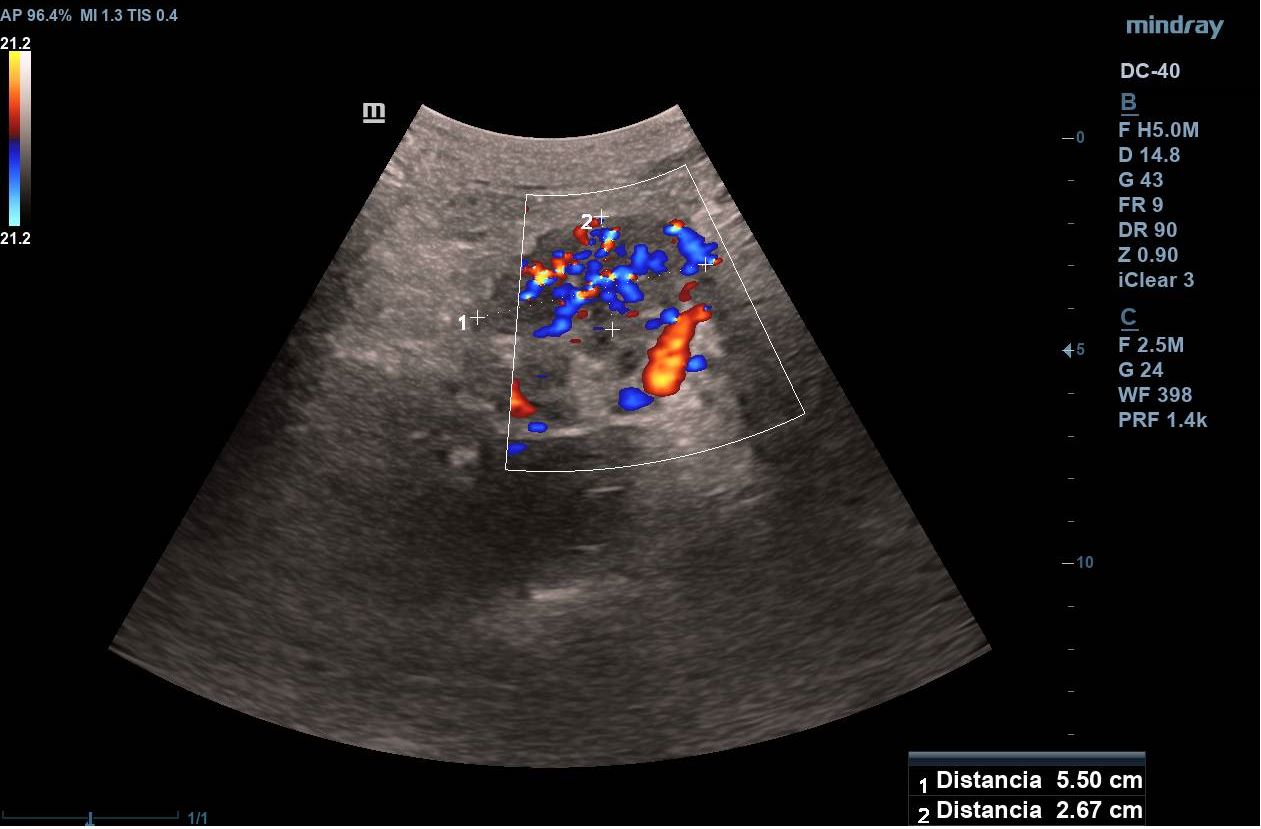

Se realiza ecografía clínica abdominal visualizando en región epigástrica masa de 5,7 x 4,6 cm de aspecto heterogéneo, con un componente principal hipoecogénico y áreas de mayor intensidad. Presenta mapa color positivo y dilatación de colédoco.

Se inicia estudio, confirmando en ecografía abdominal reglada la presencia de una masa sólida en cabeza-cuello pancreático de 5 x 4 cm con dilatación de la vía biliar intra y extrahepática y en TAC toraco-abdomino-pélvico masa hipervascular en cabeza y cuerpo pancreático con áreas de degeneración quística, dilatación del árbol biliar y atrofia del páncreas distal. Posteriormente, se realiza una ecoendoscopia en la que se informa de una masa pancreática con engrosamiento de la papila duodenal, así como dilatación de la vía biliar extrahepática.